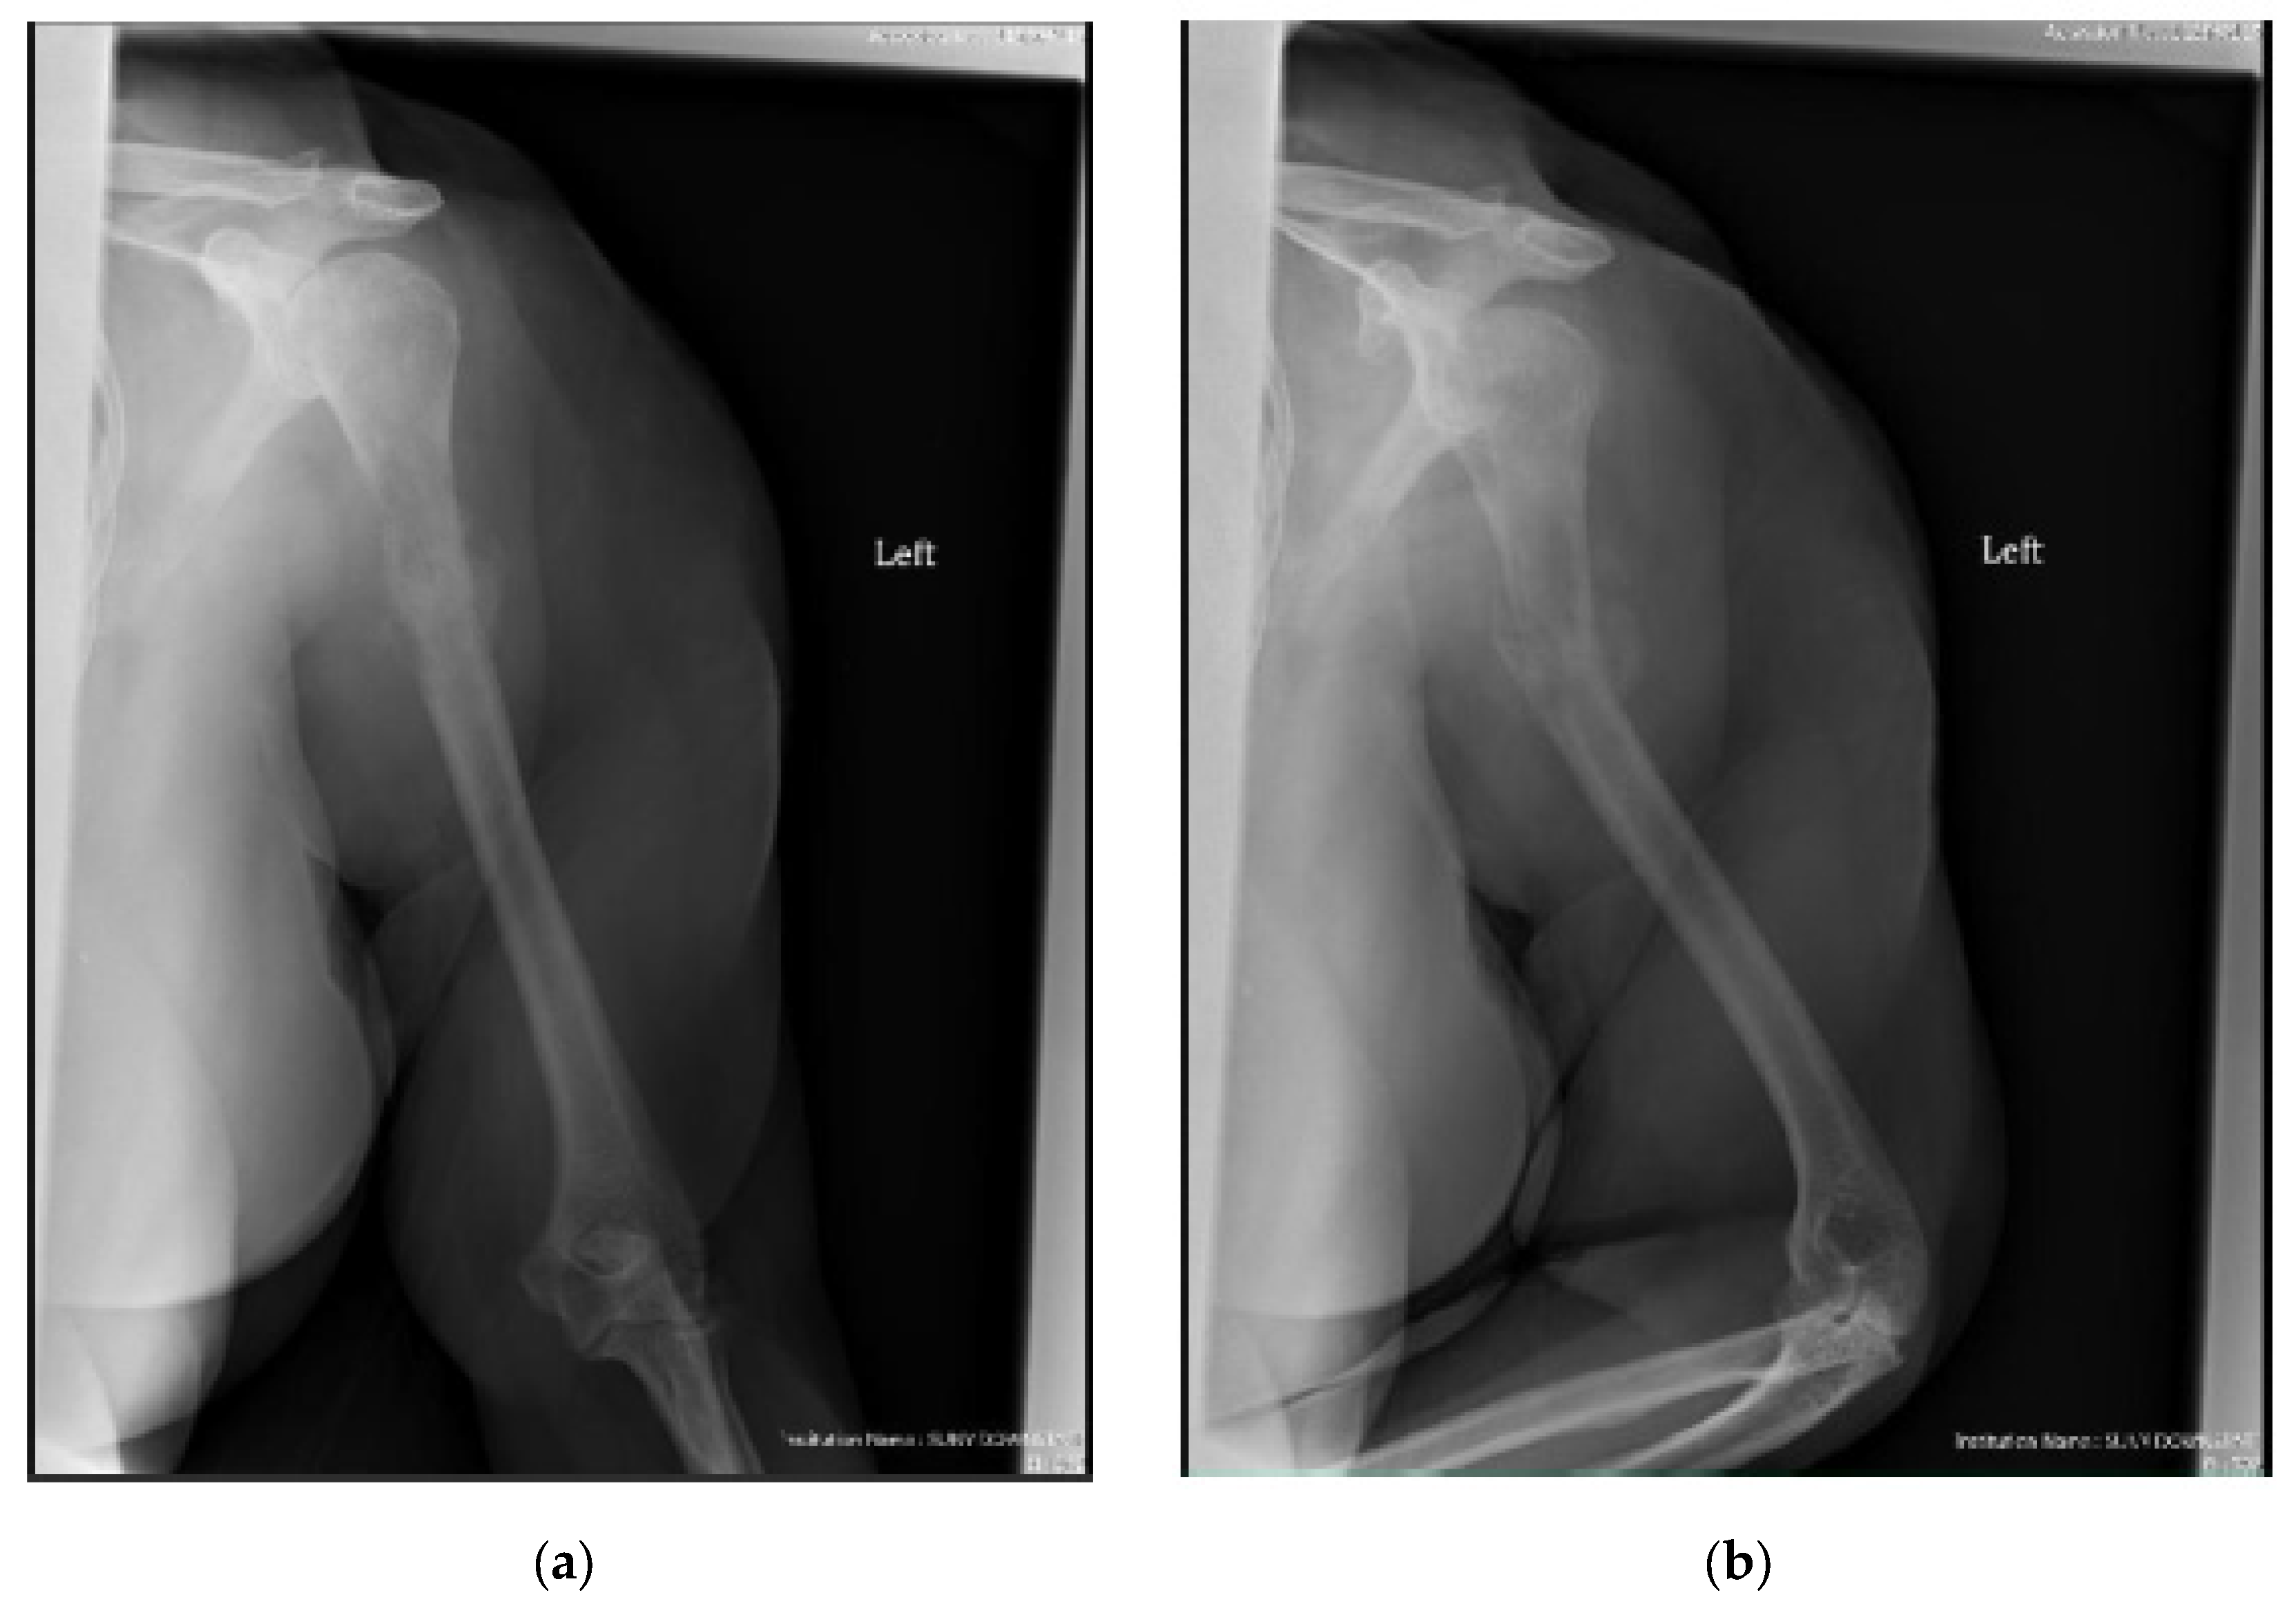

Figure 2.

(a) AP and (b) lateral right humerus radiographs of a 67-year-old male with a mixed lytic sclerotic lesion in the proximal meta-diaphyseal region, with a pathologic fracture from a newly diagnosed metastatic prostate cancer. This was treated by a bone biopsy, followed by a cemented IMN with two proximal inter-locking screws and no distal screw, as shown in the (c) AP and (d) lateral humerus radiographs. Cement was used for augmentation, due to poor proximal humerus bone quality, to support the nail and the inter-locking screws.